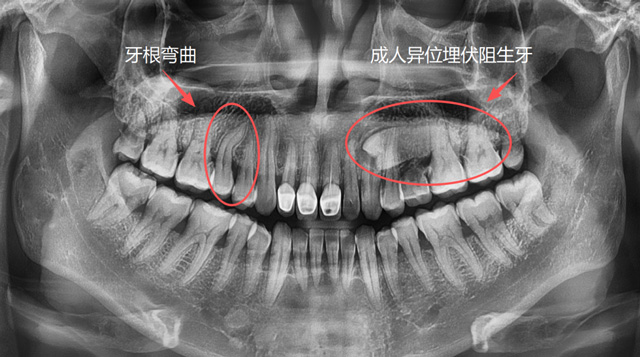

成人牙根弯曲、异位埋伏阻生牙

想要让一颗牙脱位,直的牙根是比较好操作的,弯的牙根因为有一定的弧度,需要顺着这个弧度来解除阻力。如果反着用力,可能会造成牙根折断,取断根需要去骨,就会损失一些牙槽骨的骨量。

为什么有的牙可以完整取出,有的牙需要切割成两三块再取出呢?原因就是因为它们的解剖结构和阻力点不同,拔牙手术的方案也有所差异。

总的来说,医生会根据牙齿的解剖结构和位置等因素去判断阻力,去分析怎么把这个阻力解除,再采用相应的手术方案和工具来完成手术。

医生怎么能知道这颗牙的情况呢?只用肉眼看是不够的,我们要通过口腔全景片、CBCT这些影像学检查资料来了解牙齿的解剖位置,了解牙根的数量和形态,以及有无根尖囊肿和炎症。

以上这些情况都需要在术前充分了解,这就是我们拔牙前要拍片检查的原因。